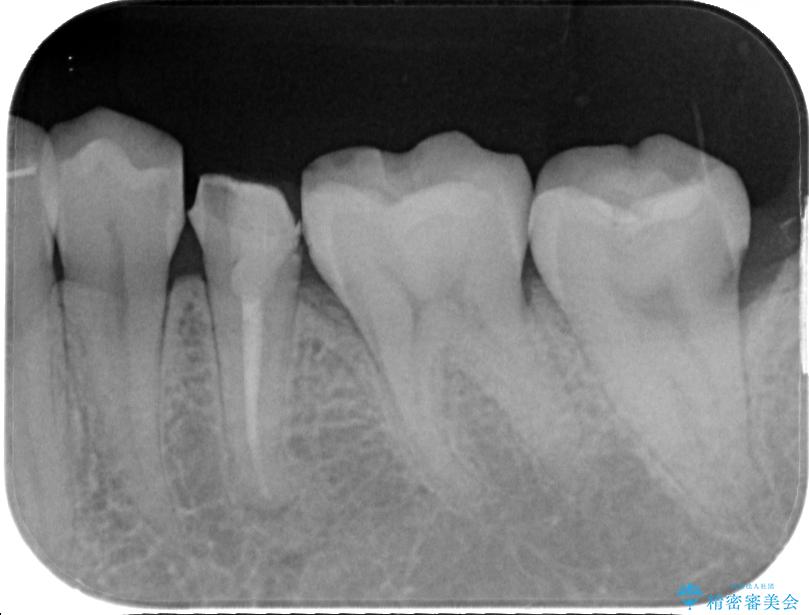

- 左下の被せものが割れたとのことで来院された患者様です。検査の結果、左下の前から4番目の歯はセラミックインレー修復、左下の5番目のところはオールセラミッククラウンによる補綴治療を行っていくことにしました。

拡大鏡視野下で被せもの、虫歯の除去を行い、オールセラミッククラウン、セラミックインレーに適した形に整えました。

患者様のご希望により左下5番目の根管治療は行っておりません。